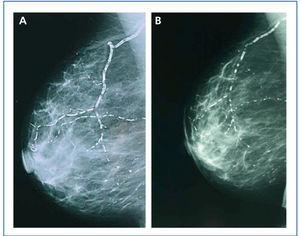

In January 2006, she presented serious SPTH, with notable increase in iPTH levels. The parathyroid ultrasound revealed an echo-rich pseudo-nodular structure in the posteriomedial area of the left thyroid lobe, compatible with parathyroid gland hypertrophy. A series of X-rays showed signs of hyperparathyroidism in the bones of both hands and wrists, with VC in radial and interdigital arteries. The mammography revealed multiple linear VC in both breasts (Figures: 1A, 2A, 3A and 4A; hand and mammary gland images in 2006).

During this period, the X-ray series showed that the interdigital artery calcifications had disappeared, and the bone appeared better structured (Figures 1B and 2B; hand X-ray, 2007). The mammography also showed regression of the VC. Initial linear calcifications were replaced by irregular calcifications (Figures 3B and 4B; mammary glands in 2007).

Regression is evident in the mammographies, where we see how linear calcification was replaced by smaller areas of patchy irregular calcification. The images show how clearly VC can be seen in the mammographies, enabling accurate follow-up of their evolution. This is therefore a useful economic and accessible technique for VC diagnosis and follow-up in women with CKD.8,27 The presence of VC in a mammography is considered a cardiovascular risk marker in the general population, which is related to atherosclerosis and diabetes mellitus. However, for the uraemic population, a recently published study establishes the existence of histological correlation between CV presence in a mammography and calcification of the medial layer in arteries.28 Whereas calcification on the arterial intima is essentially related to atheromatosis and inflammation, medial artery calcification has a greater relation to CKD and associated metabolic disorders.5 In this case, given that it is a young woman without additional cardiovascular risks, one might consider that the calcification present in the mammary glands was more related to CKD and mainly affected the medial layer. Were this the case, regression of the mammary calcifications observed could be justified by the correct control of MBD-CKD disorders, since this regression would be unlikely in other patients in whom the VC at the arterial intima and media layers converge due to the interaction of many other factors, thus making the desired regression difficult to achieve.

Figure 3. (A) Anteroposterior X-ray of mammary gland in 2006. (B) Anteroposterior X-ray of mammary gland in 2007

Figure 4. (A) Craniocaudal breast X-ray in 2006. (B) Craniocaudal breast X-ray in 2007